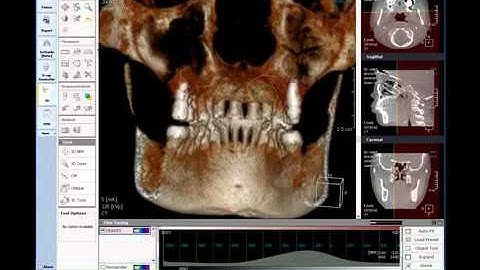

OnDemand3D Tool Tip - CPR(3D module)